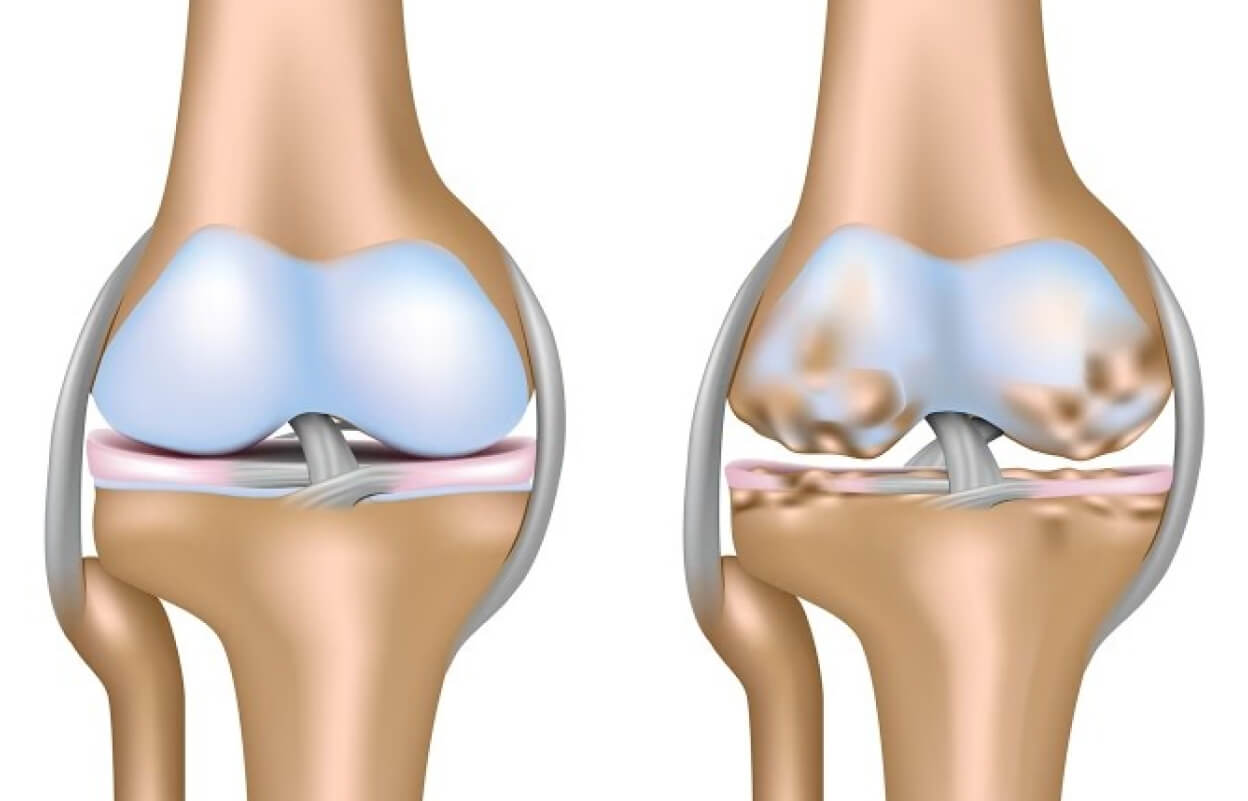

Артроз (остеоартроз, остеоартрит) — это хроническое прогрессирующее заболевание суставов, при котором разрушается суставной хрящ, происходят изменения в костной ткани и воспаляется суставная капсула. В здоровом суставе гладкий хрящ покрывает концы костей, обеспечивая плавное безболезненное скольжение. При артрозе хрящ истончается, трескается, теряет эластичность, а затем полностью разрушается, обнажая кость.

Сравнение здорового сустава и сустава с артрозом у собаки